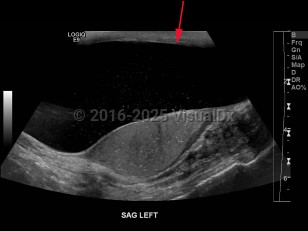

Hydrocele of testis

A hydrocele is an accumulation of serous fluid between the visceral and parietal layers of the tunica vaginalis, which covers the testes and spermatic cord. Hydroceles may be communicating or noncommunicating. A communicating hydrocele results from failure of closure of the tunica vaginalis leaving a patent process. This is most common in newborns. The fluid is often reducible. Noncommunicating hydroceles have no connection to the peritoneal cavity and are not reducible.

A hydrocele often presents as a painless visible or palpable cystic mass in the scrotum and otherwise is usually asymptomatic.

Typically, a male newborn patient presents with painless scrotal swelling on one or occasionally both sides. Usually, the hydrocele will go away on its own within the first year of life without medical intervention. An adult man who presents with a hydrocele may experience discomfort, a feeling of heaviness or fullness, or induration and irritation of the scrotal skin.